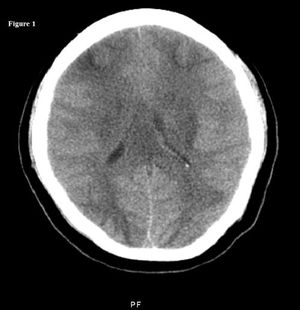

A young woman was admitted at 36 weeks' gestation with severe preeclampsia. During delivery, she experienced generalized seizures. She remained postictal throughout the normal vaginal birth.